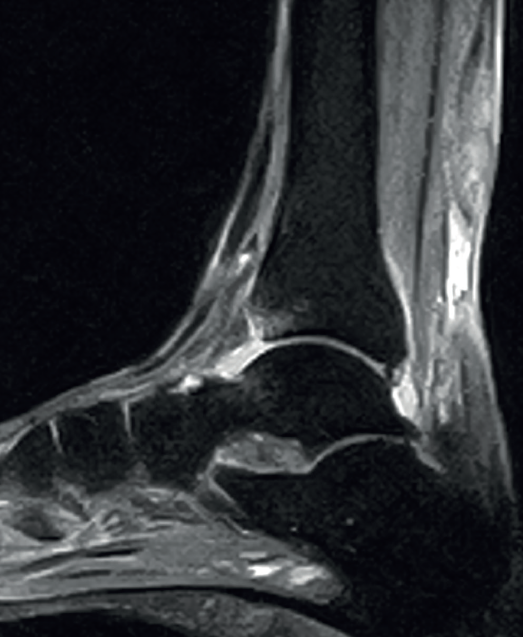

Figure 1. Insertional Achilles tendinopathy associated to retroachilleal bursitis and Haglund deformity.

With regard to the pathological ultrasound findings (Table 1), non-insertional Achilles tendinopathy (2-6 cm from the calcaneal insertion) (Figure 1) is characterized by a spindle-form thickening of the tendon area, hypoechoic areas and disruption of the fibrillar pattern that can correspond to degeneration or partial rupture(24,28). Increased vascularization of the peritendinous ventral portion may also be present(5,6,30).

However, in the chronic forms of insertional Achilles tendinopathy or enthesopathy (present in the distal 2 cm of the tendon), we can observe calcifications within the tendon in the form of traction enthesophytes or at the insertion site in the form of spurs. These conditions are often associated to alterations of the retroachilleal bursa(5,31)(Figure 2).

Retrocalcaneal bursitis is characterized by an increased volume of the bursa, with the possible association of Haglund deformity(25). In the case of retroachilles or superficial calcaneal bursitis we can identify fluid between the skin and the Achilles tendon(5).